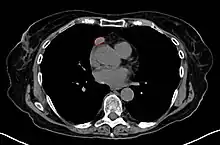

When a thymoma is suspected, a CT/CAT scan is generally performed to estimate the size and extent of the tumor, and the lesion is sampled with a CT-guided needle biopsy. Increased vascular enhancement on CT scans can be indicative of malignancy, as can be pleural deposits.[1] Limited biopsies are associated with a very small risk of pneumomediastinum or mediastinitis and an even-lower risk of damaging the heart or large blood vessels. Sometimes thymoma metastasize for instance to the abdomen.[5]

An encapsulated cystic thymoma.

A locally invasive circumscribed thymoma (mixed lymphocytic and epithelial, mixed polygonal and spindle).